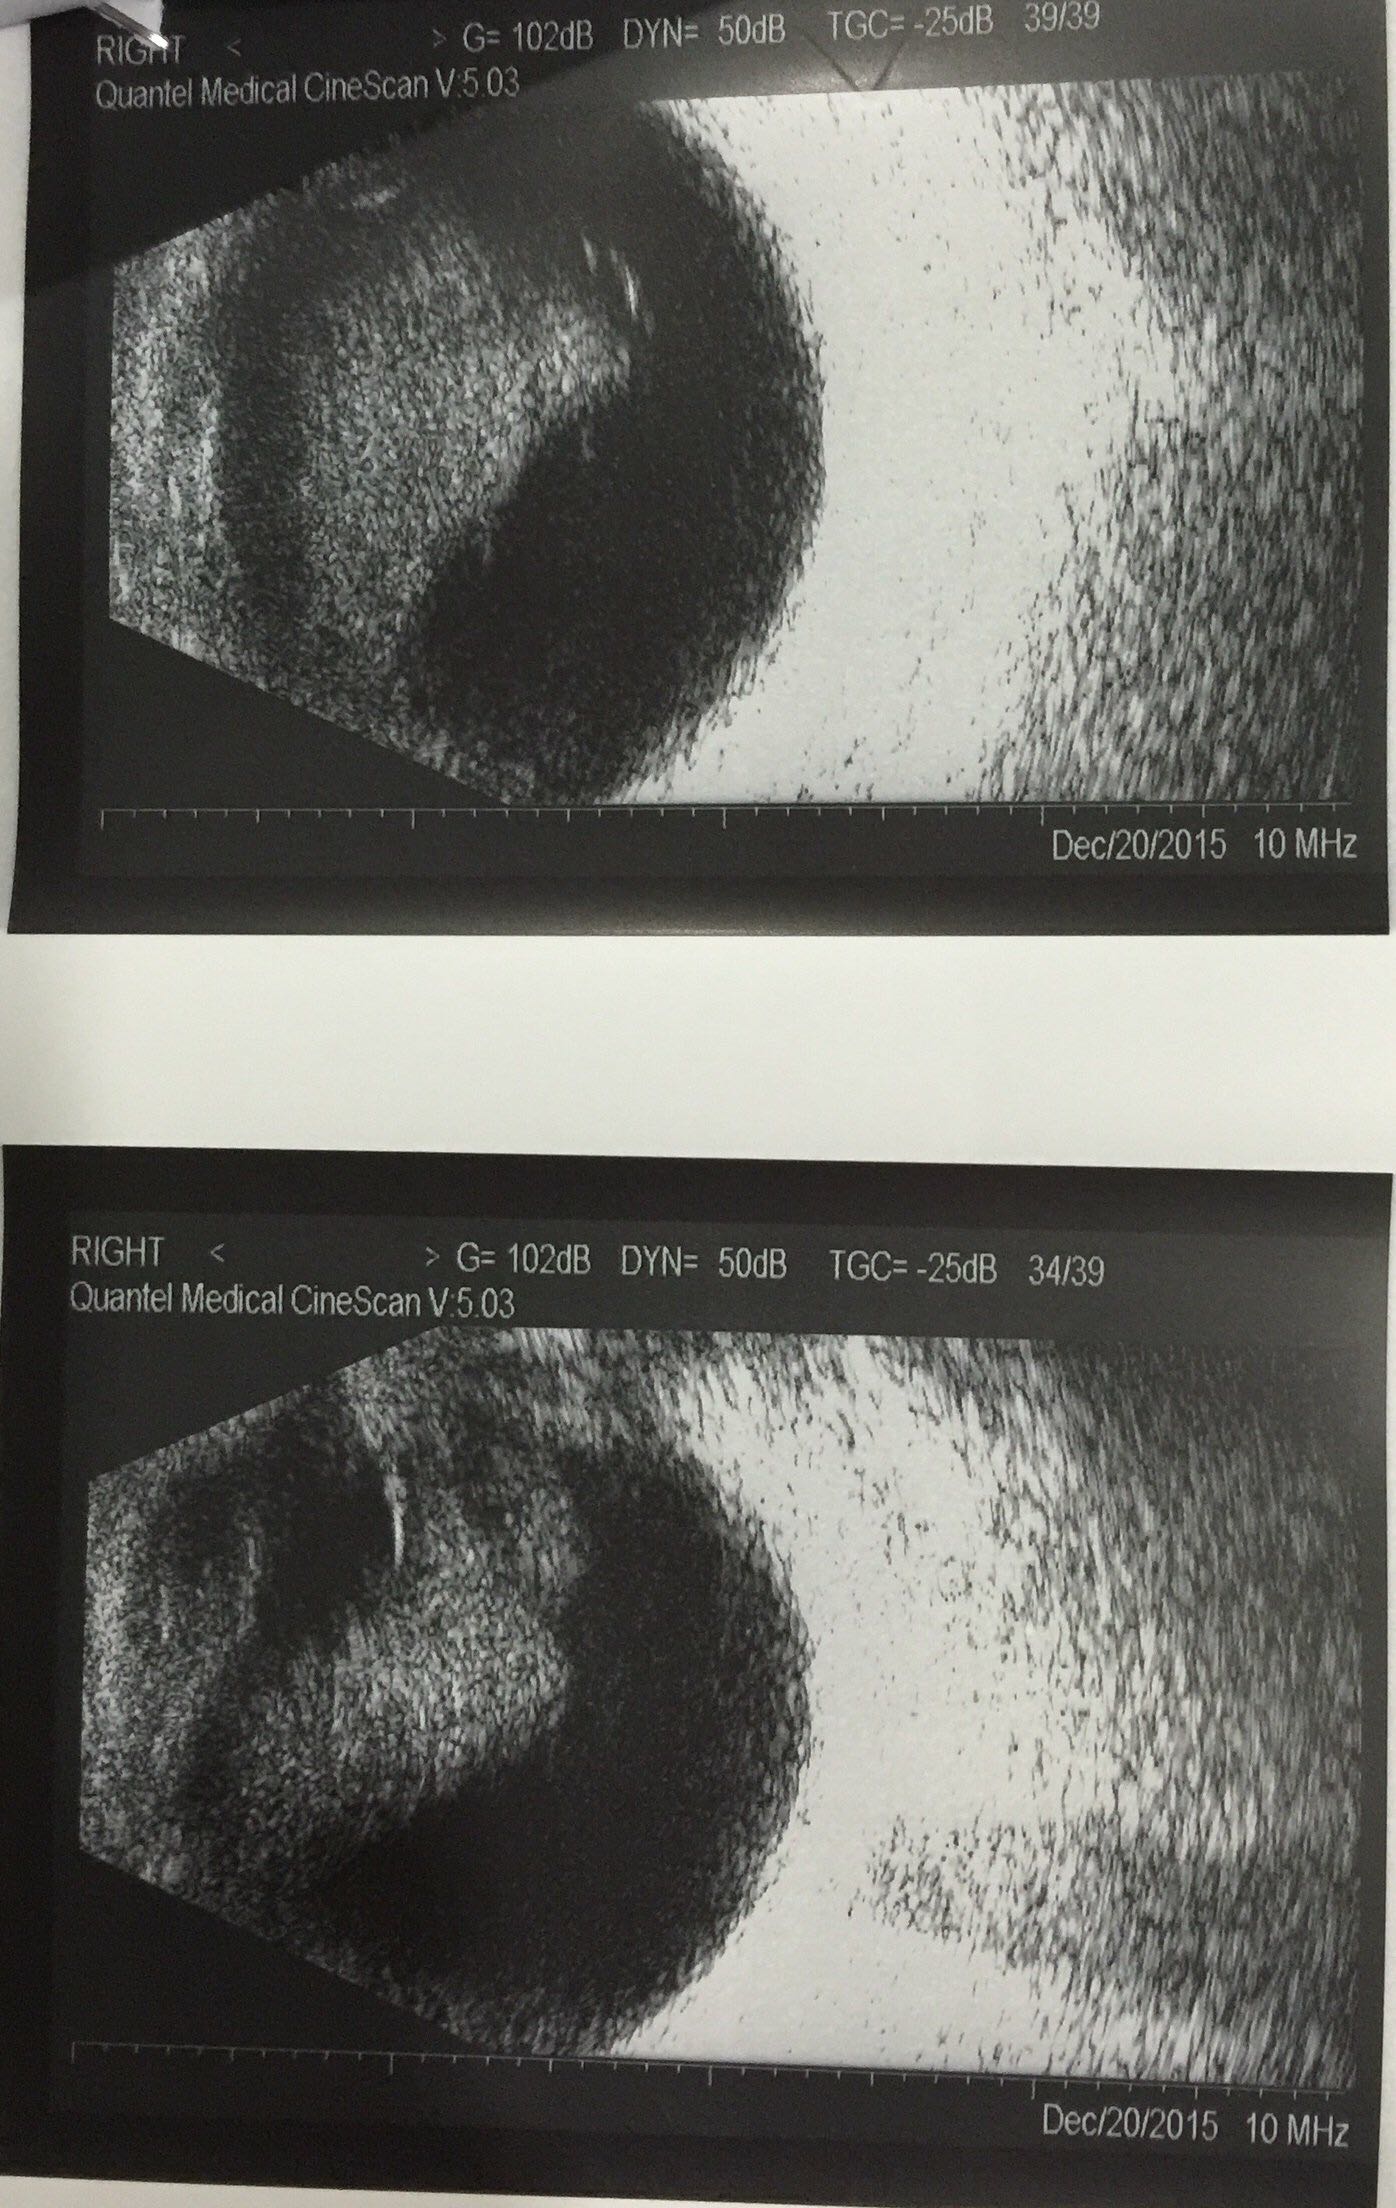

双眼星状玻璃体变性一例

张某,男,77岁,因 “双眼视力下降3个月”就诊。既往无特殊病史,无家族遗传史。

右眼视力0.6,左眼视力0.4,眼压右10.左11,双外眼无特殊,双眼晶体混浊,c0n2p1。双眼玻璃体眼底查体见图

双眼星状玻璃体变性,双眼白内障。

该患者左眼是否考虑行白内障联合微创玻璃体切除术?